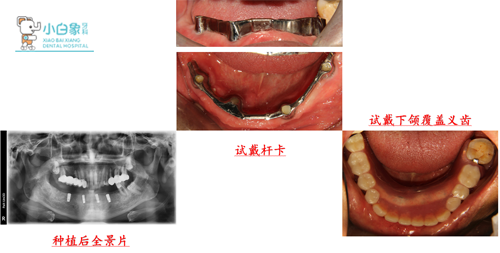

下颌余留牙拔除后行种植覆盖义齿修复

治疗过程:上颌13,14,15,16,17行根管治疗后,制备牙体后行联冠修复,25,26,27根管治疗后行冠修复。47局麻下开髓揭顶行根管治疗,树脂充填。 局麻下拔除余留牙。

设计思路:33,35,43,46数字种植导板指导下精确种植

手术过程:

半年后复诊